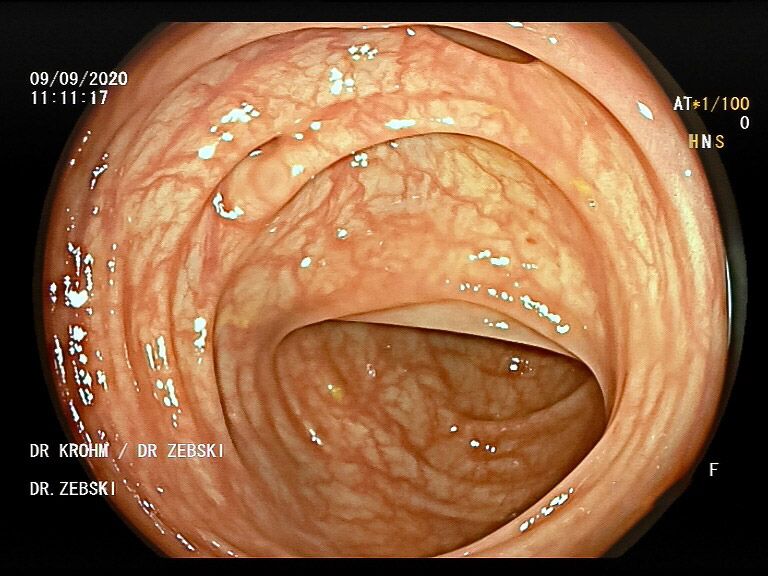

Die Darmspiegelung ist der uneingeschränkte Goldstandard für die Diagnostik und Vorsorge sämtlicher Erkrankungen des Dickdarms und des untersten Dünndarms. Die hochauflösende Bildqualität (High Definition) unserer modernen Videokoloskope ermöglicht eine zuverlässige Einordnung nahezu sämtlicher entzündlicher oder geschwulstiger Veränderungen der Dickdarmschleimhaut.